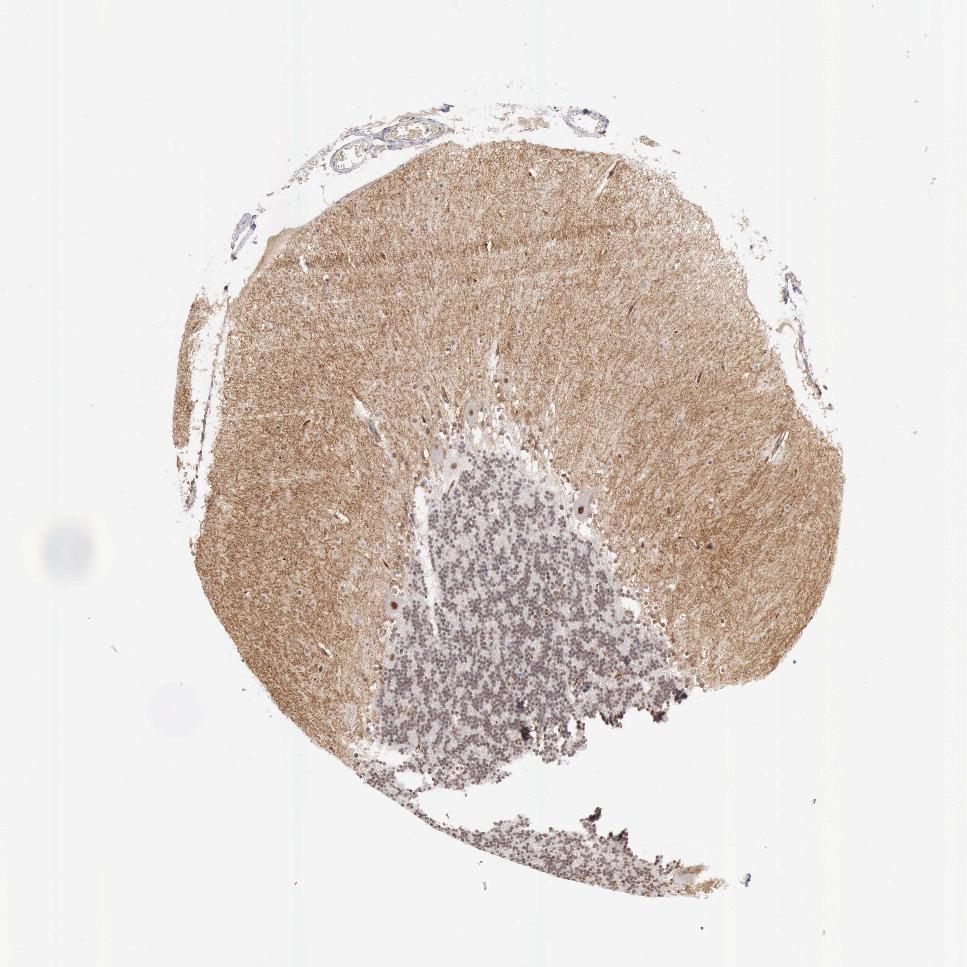

CEREBELLUM - Antibody stainingi

Antibody staining in the annotated cell types in the current human tissue is reported as not detected, low, medium, or high, based on conventional immunohistochemistry profiling in selected tissues. This score is based on the combination of the staining intensity and fraction of stained cells.

Each image is clickable and will lead to virtual microscopy that enables deeper exploration of all samples and also displays staining intensity scores, fraction scores and subcellular localization as well as patient and tissue information for each sample.

Antibody HPA028598Antibody CAB000153

Purkinje cells HighHigh

Cells in granular layer MediumLow

Cells in molecular layer LowNot detected